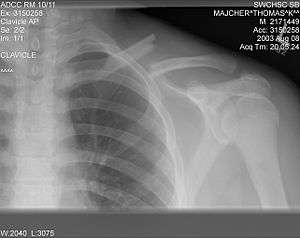

The basic method to check for a clavicle fracture is by an X-ray of the clavicle to determine the fracture type and extent of injury. In former times, X-rays were taken of both clavicle bones for comparison purposes. Due to the curved shape in a tilted plane X-rays are typically oriented with ~15° upwards facing tilt from the front. In more severe cases, a computerized tomography (CAT) or magnetic resonance imaging (MRI) scan is taken. However, the standard method of diagnosis through ultrasound imaging performed in the emergency room may be equally accurate in children.[1]